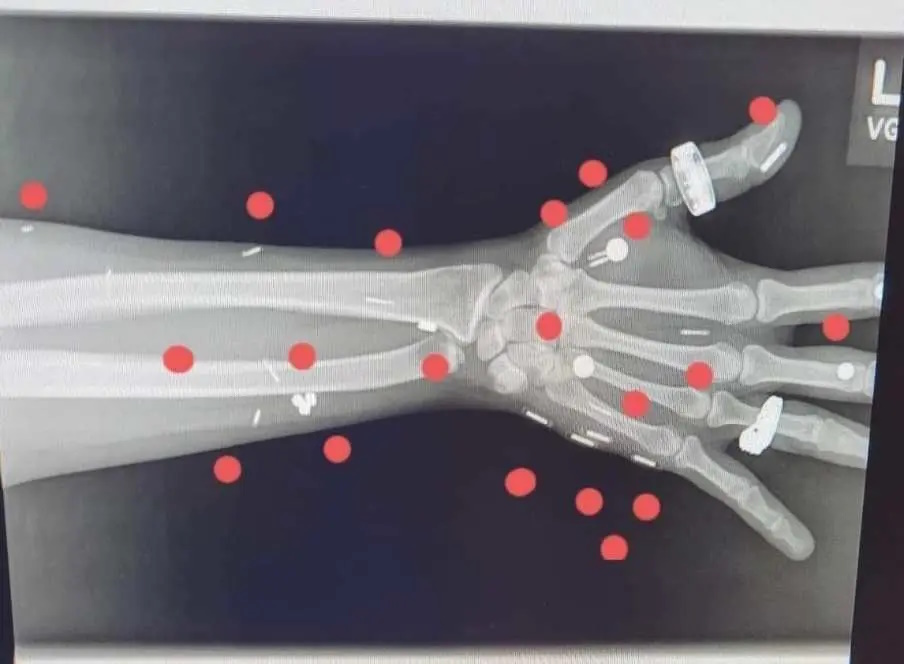

او برای این که بتواند رکورد گینس را به نام خود ثبت کند ناچار به تهیه لیستی از کارهایی می بود که این تراشهها انجام خواهند داد و اسکنهایی که نشاندهنده وجود آنها در بدن او باشد.

به حرف های خودش بزرگترین ایمپلنتی که دارد ۶.۳۵ سانتیمتر طول و ۱.۲۷ سانتیمتر ضخامت دارد و مورد منفعت گیریترین آنها تراشهای در دستش است که با آن در جلوی خانهاش را باز میکند.

نزدیک به نیمی از ایمپلنت های او میکروچیپ هایی می باشند که برای ترقی حواس و توانایی های خود از آنها منفعت گیری میکند؛ همانند باز کردن قفل ها و روشن کردن کامپیوتر.

بقیه آهنربایی می باشند و به او «حس ششم» خواهند داد؛ همانند حس کردن سیم های برق پشت دیوار و این که آیا ترنسفورماتور یا جعبه برق، قادر به دریافت برق هست یا خیر. سین میگوید: «من میتوانم فهمید شوم که آیا مایکروویو شما بیشتر از حد اشعه متساعد میکند یا نه و این را با لرزش دستم میفهمم. اشکار کردن قطعه گمشده پشت گوشواره هم یکی از چیزهایی است که در طول سالیان زیاد به کارم آمده است.»